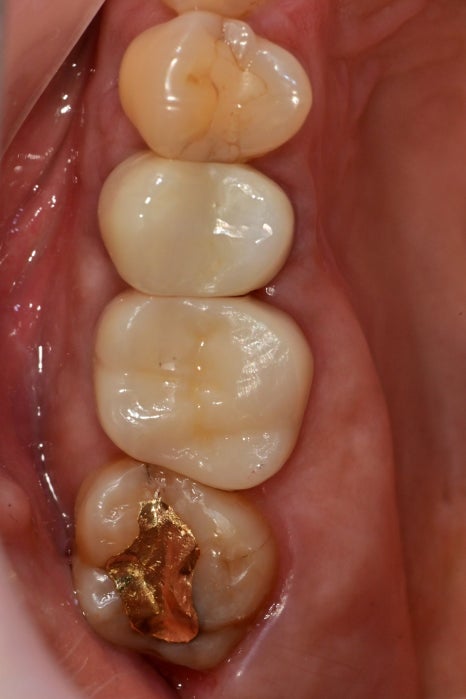

오늘 소개해 드릴 케이스는

치아에 다발성 크랙이 발견되고

치아파절까지 관찰된 환자분입니다.

구강 내에서는 아래쪽 뿐 아니라

대합 되는 부위에서도 다발성의 크랙이 관찰되었습니다.

치아의 파절과

좌우로 진행된 금간 부위 하방으로

2차 우식까지 진행되었습니다.

금간 부위와 충치를 제거하는 도중에 안쪽까지 발견된

크랙을 발견할 수 있었습니다.